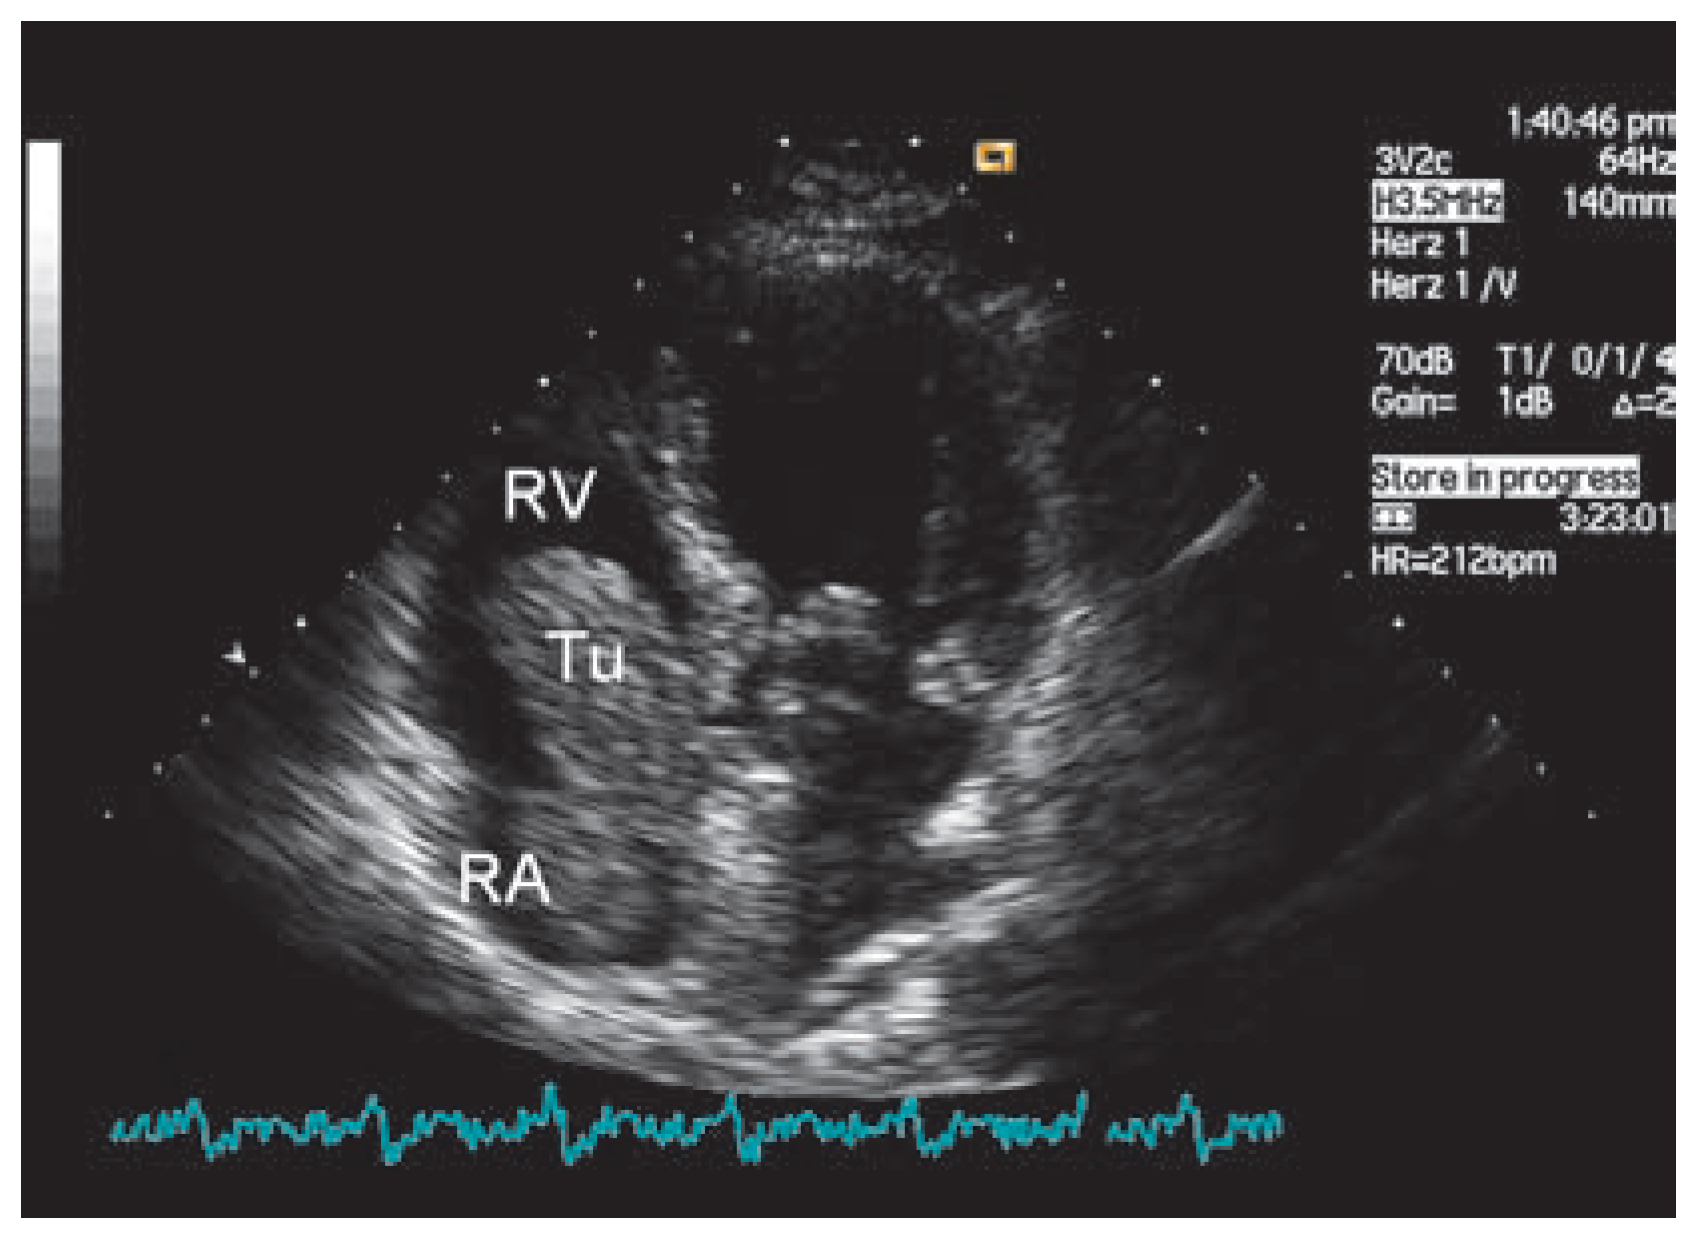

Endometrial Stromal Sarcoma—A Rare Tumor Invading the Heart

Findings, diagnosis and discussion